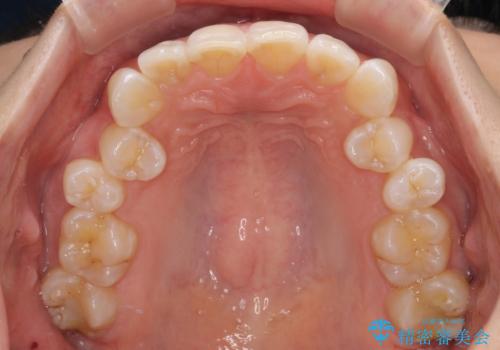

- 上下前歯のデコボコとディープバイトを気にして来院された患者様です。

歯列全体に叢生があり、舌の突出癖が認められたため、突出癖が改善されない場合には口元が突出するリスクが考えられました。